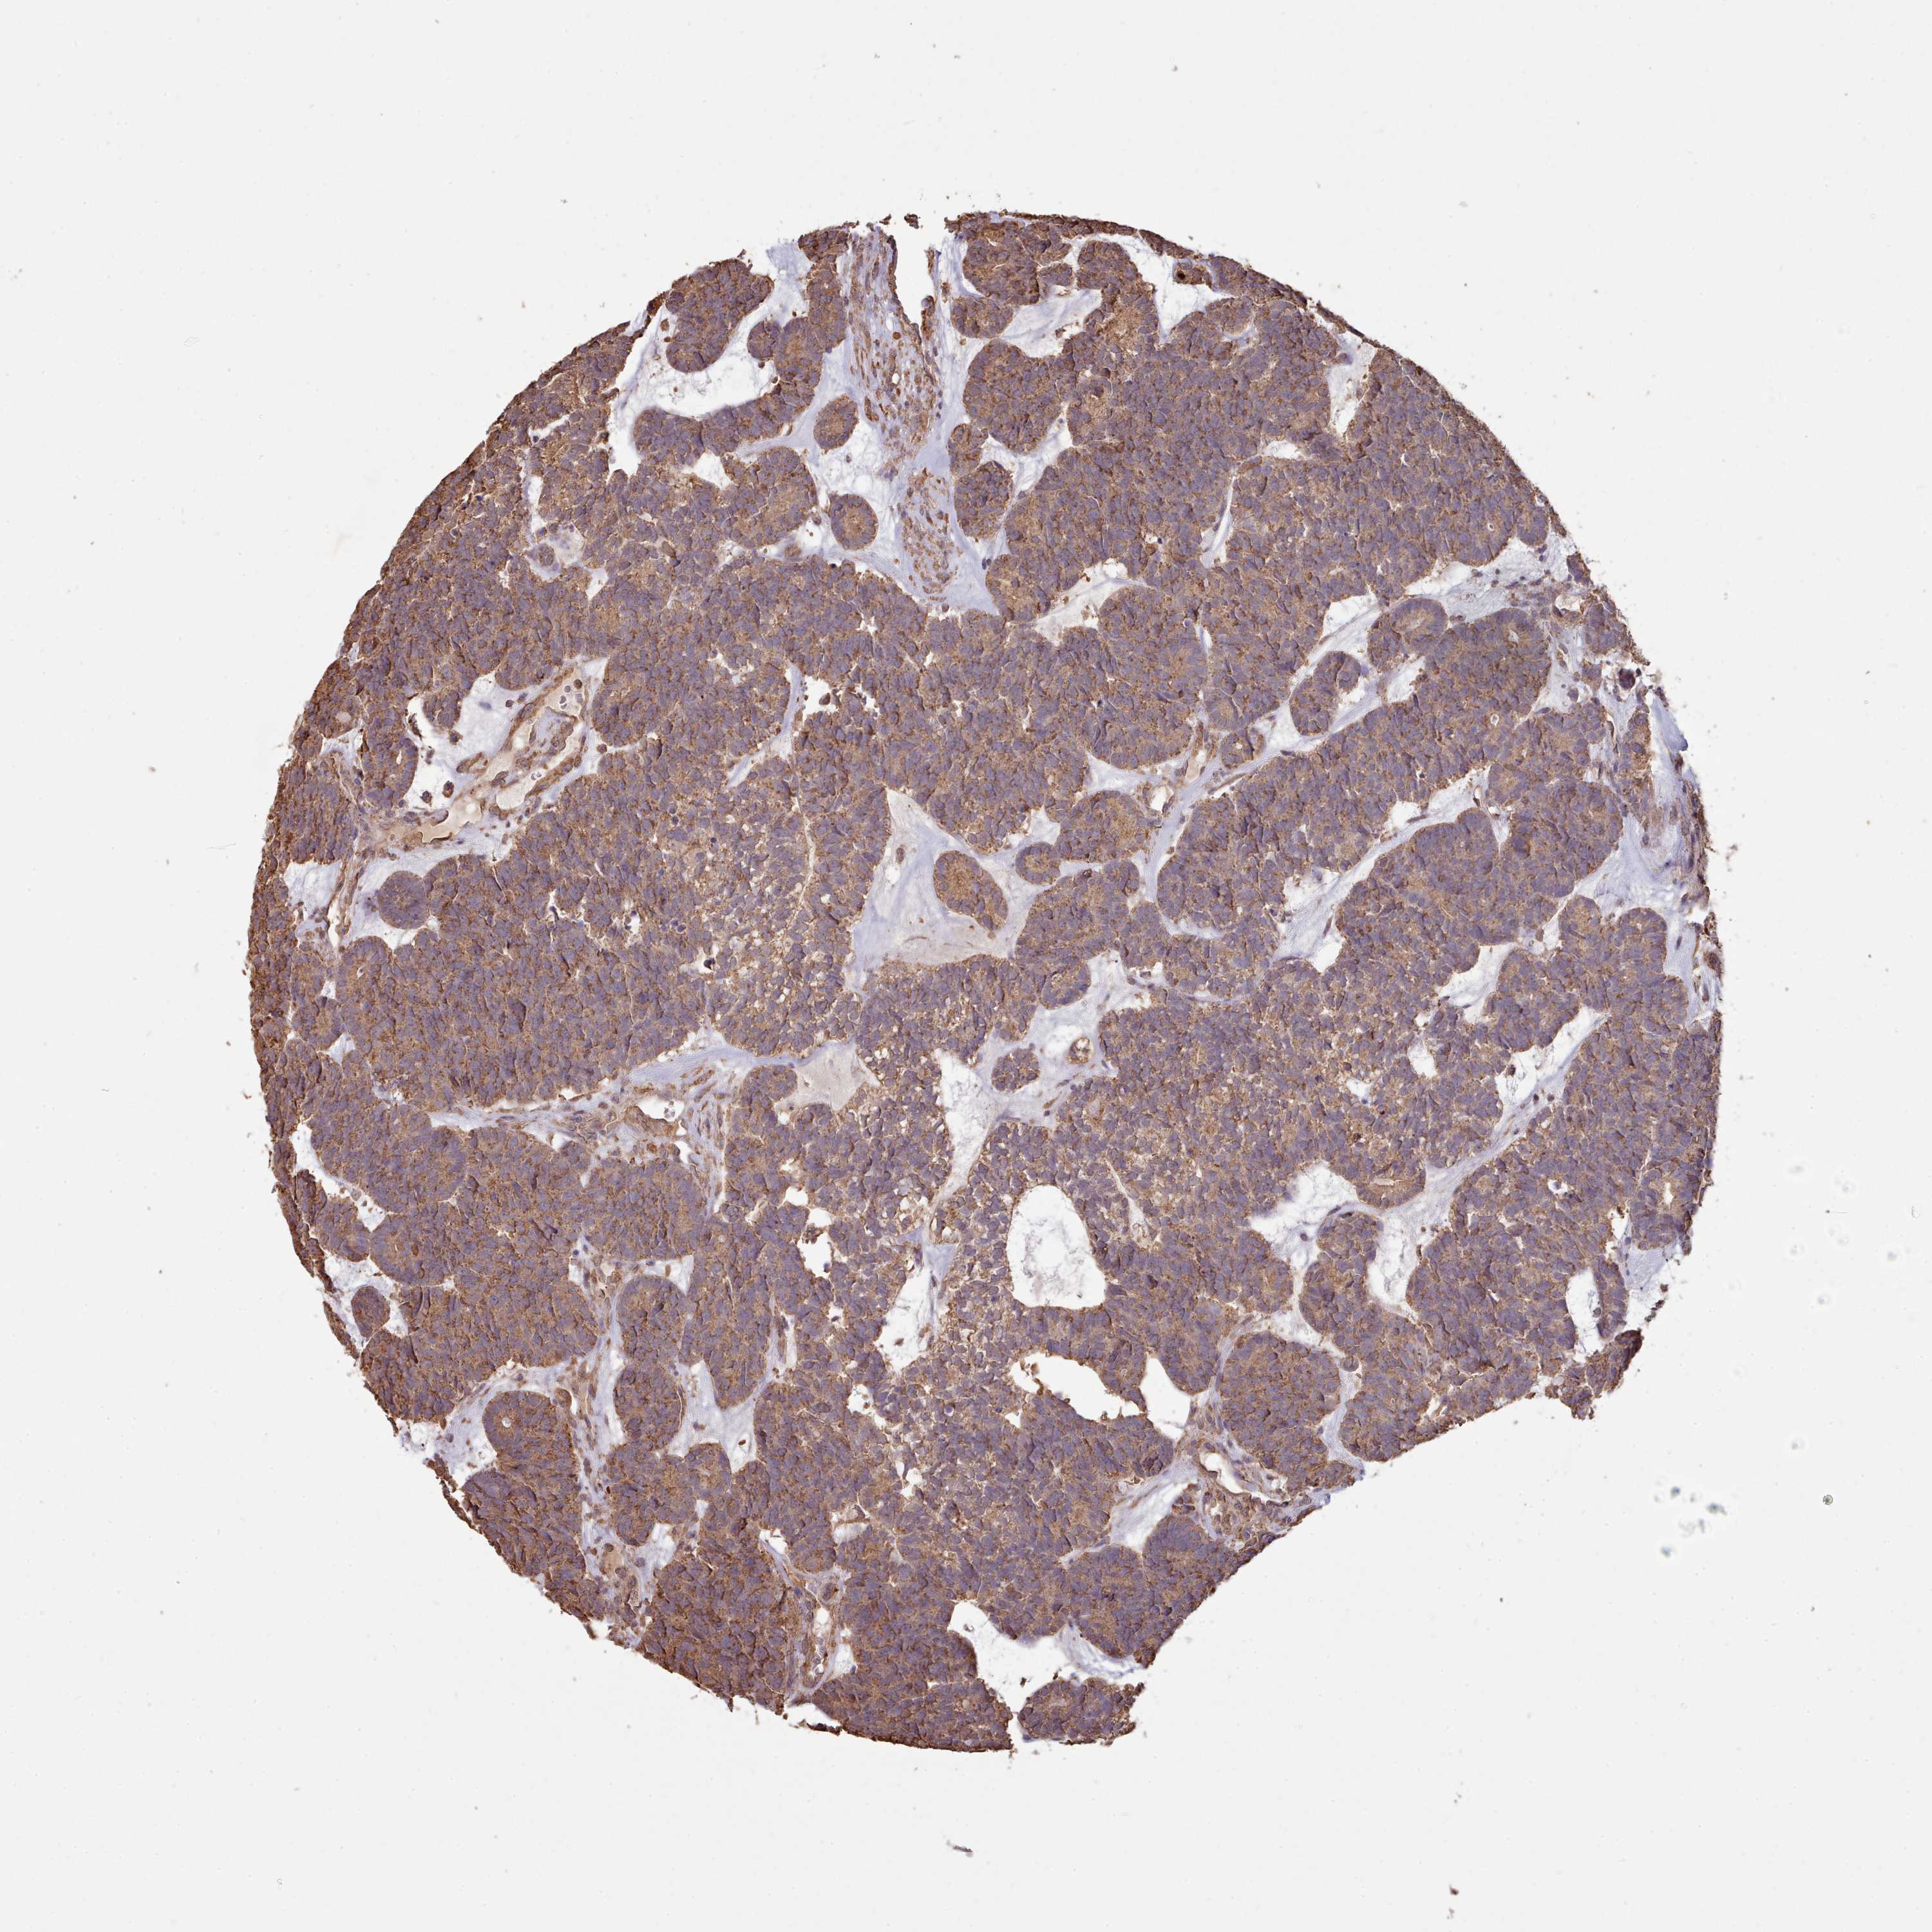

HEAD AND NECK CANCER - Protein expressioni

A mouse-over function shows sample information and annotation data. Click on an image to view it in a full screen mode. Samples can be filtered based on level of antibody staining by selecting one or several of the following categories: high, medium, low and not detected. The assay and annotation is described here.

Antibody stainingi

Antibody staining in the annotated cell types in the current human tissue is reported as not detected, low, medium, or high, based on conventional immunohistochemistry profiling in selected tissues. This score is based on the combination of the staining intensity and fraction of stained cells.

Each image is clickable and will lead to virtual microscopy that enables deeper exploration of all samples and also displays staining intensity scores, fraction scores and subcellular localization as well as patient and tissue information for each sample.

Antibody HPA051164

Staining

High

Medium

Low

Not detected

Intensity

Strong

Moderate

Weak

Negative

Quantity

>75%

75%-25%

<25%

None

Location

Nuclear

Cytoplasmic/membranous

Cytoplasmic/membranous,nuclear

Squamous cell carcinoma, NOS